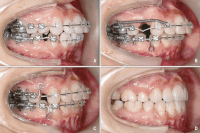

Với phương pháp niềng răng mắc cài kim loại, các nha sỹ sẽ áp dụng mắc cài kim loại tạo hợp với dây thun định hình chuyên dùng trong nha khoa để tạo lực tác động giúp di chuyển những răng lệch, nhô hay thụt vào bên trong đến vị trí phù hợp để cân bằng hàm răng.

đặc thù nó có thể áp dụng cho đông đảo các nếu răng như: Răng bị hô, răng bị móm, răng bị lệch lồi ra thụt vào và sai khớp cắn,… mà giá thành lại vô cùng hợp lí.